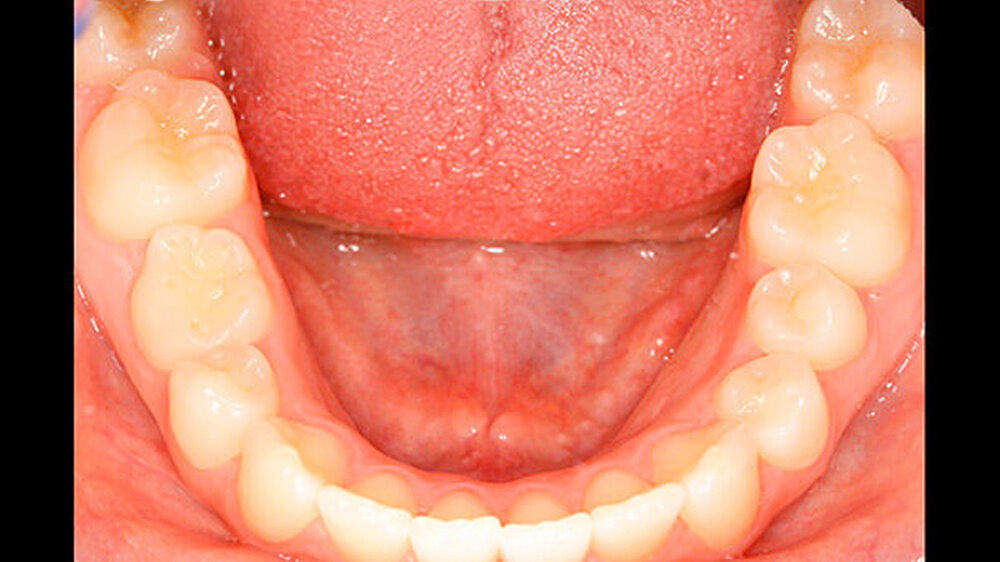

Die Patientin zeigte ein kariesfreies bleibendes Gebiss mit Nichtanlage des Zahns 35 und Persistenz des Zahns 75 auf (Abbildung 1). Sie wies im Frontzahnbereich sowie im rechten Seitenzahnbereich eine Klasse I auf, im linken Seitenzahnbereich aufgrund der Größe des Zahns 75 eine Klasse II. Zahn 75 befand sich in deutlicher Infraokklusion (Abbildung 2). Der Perkussionstest wies allerdings nicht eindeutig auf eine Ankylosierung hin.